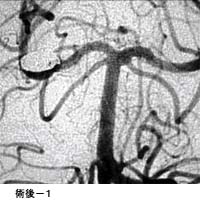

破裂脳動脈瘤に対するコイル塞栓術GODコイルだとちょっと古いので、コイル塞栓術とする方が良いのではないかと思います。

術後 コイルにより動脈瘤が写らなくなりました。